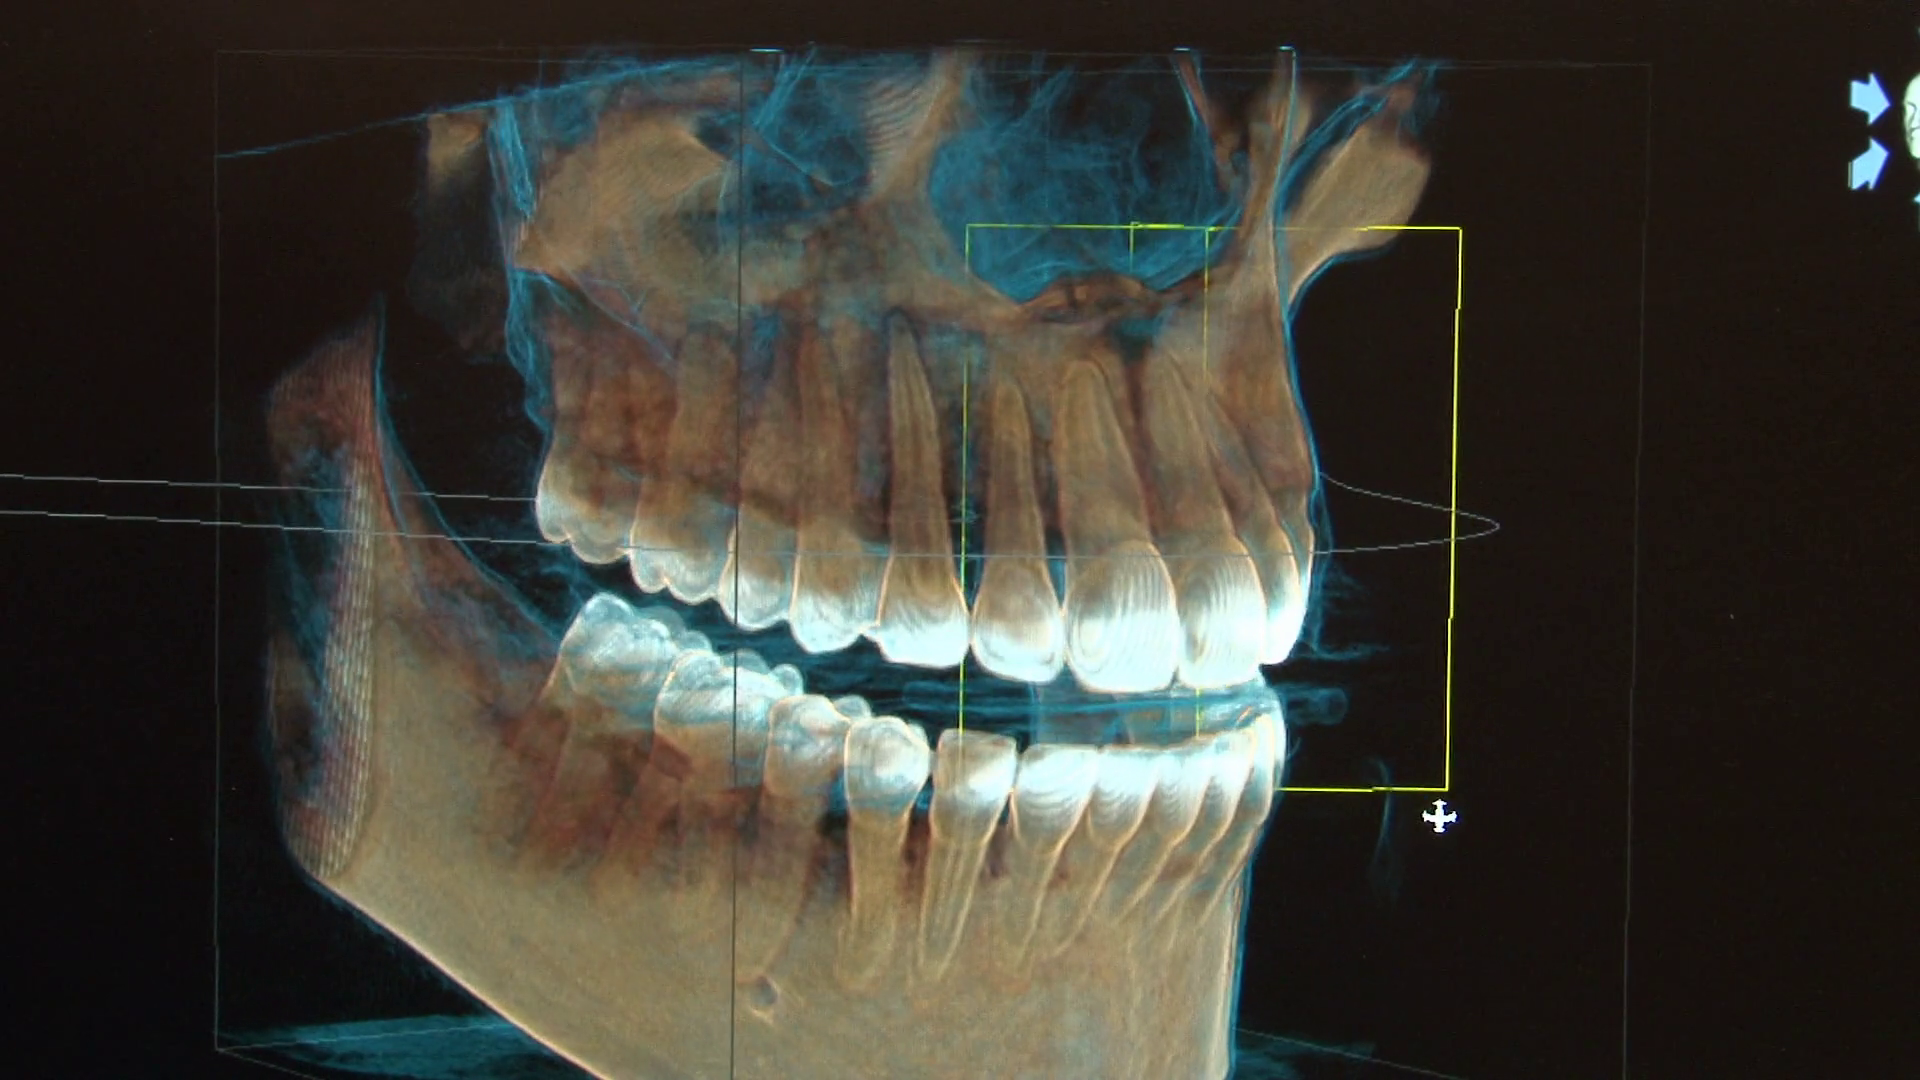

Clinica noastră stomatologică de familie oferă îngrijire completă și personalizată pentru toate vârstele, într-un mediu prietenos și relaxant. Punem accent pe prevenție, educație și tratamente moderne, folosind tehnologii de ultimă generație pentru a asigura confortul și siguranța fiecărui pacient. Echipa noastră de medici dedicați are o abordare empatică, bazată pe încredere și comunicare deschisă. Fie că este vorba de un control de rutină, tratamente estetice sau intervenții complexe, scopul nostru este să redăm zâmbetul sănătos și încrederea fiecărui membru al familiei.